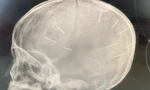

Thực hiện chỉ đạo trên, Đội Điều tra trọng án Phòng CSHS, Công an TP Hà Nội tiếp nhận hồ sơ từ Công an huyện Thạch Thất, phối hợp với Viện KSND TP Hà Nội điều tra. Trước đó, ngày 18/1, Công an huyện Thạch Thất tiếp nhận tin báo về việc bé A nhập viện trong tình trạng hôn mê. Qua chụp chiếu, bệnh viện xác định trong hộp sọ của bé có 9 vật thể cứng giống chiếc đinh. Ngay lập tức, Công an huyện đã vào cuộc xác minh, triệu tập chị N.T.L (27 tuổi, mẹ cháu bé) và lấy lời khai của những người liên quan.

Ngày 17/1, Bệnh viện Đa khoa Thạch Thất tiếp nhận bé A. trong tình trạng hôn mê, co giật. Sau khi tiến hành chiếu chụp, chẩn đoán trên phim có hình ảnh cản quang trên hộp sọ bệnh nhi. Sáng hôm sau, bé A. được chuyển đến Bệnh viện Đa khoa Xanh Pôn chụp cắt lớp, phát hiện có 9 dị vật trong hộp sọ, hình dạng giống như chiếc đinh. Bé A. đang điều trị ở khoa Hồi sức Nhi, tình trạng rất nguy kịch…